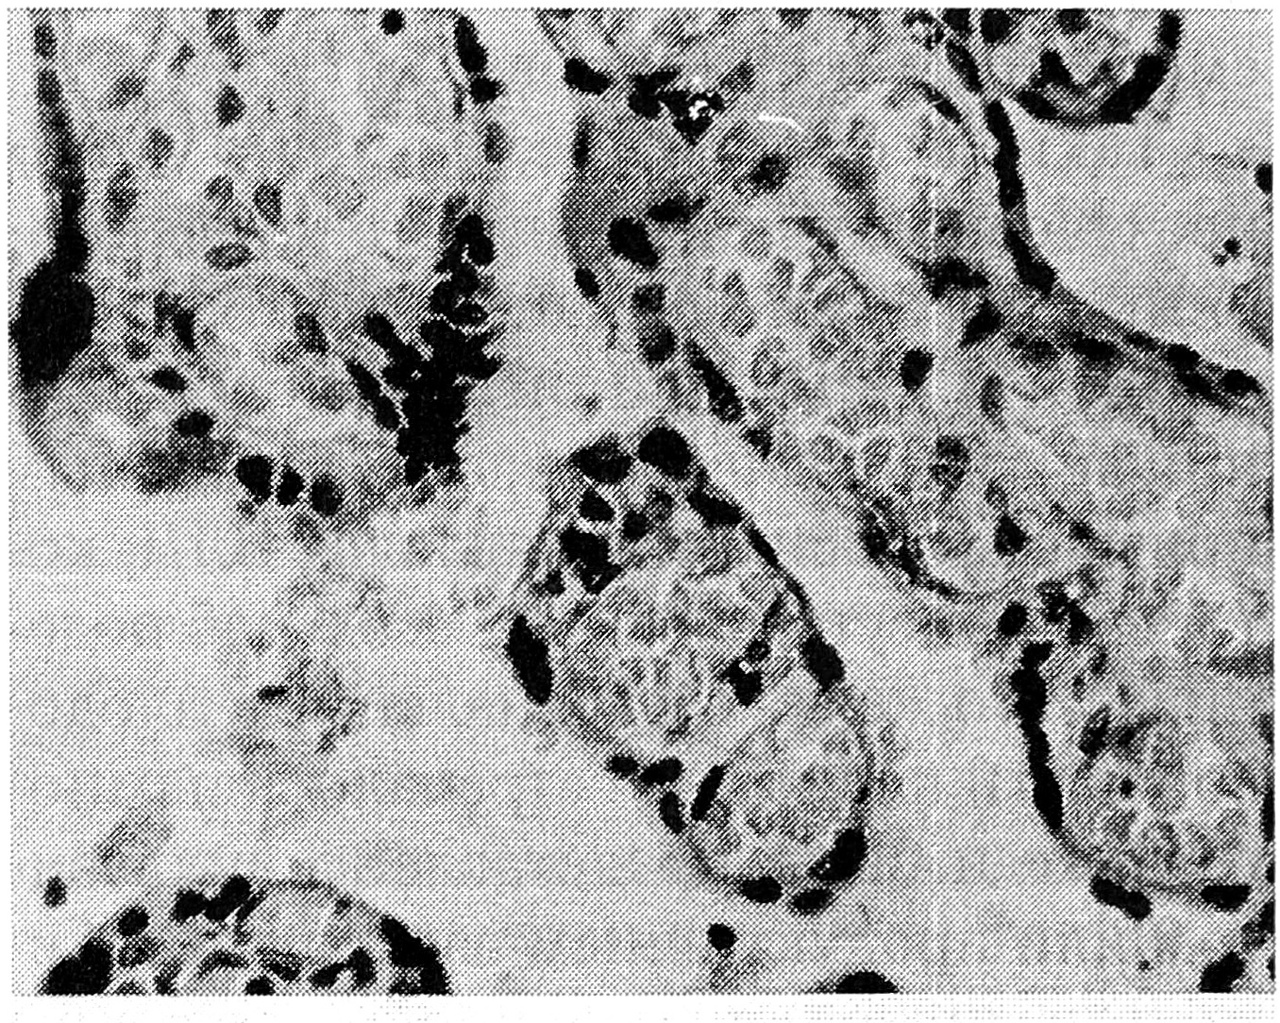

Рис. 1. Базальный лимфоцитарный децидуит при хламидиозе (этот и последующий препараты плаценты окрашены гематоксилин-эозином): а — умеренная инфильтрация лимфоцитами базальной пластинки, х 400; б — многоядерные симпласты в базальной пластинке, х 400.

Во всех 75 плацентах был выявлен базальный лимфоцитарный децидуит (БЛД), который по интенсивности лимфоидной инфильтрации варьировал от мнимального до тяжелого (рис. 1а). В зависимости от патогенности возбудителя и, вероятно, от длительности заболевания воспалительный процесс протекал по одному из двух вариантов развития [3]. Первый вариант БЛД характеризовался преобладанием дистрофии и лизиса децидуальных клеток, уменьшением количества клеток цитотрофобласта. Иногда превалировали гемодинамические изменения с развитием в базальной пластинке отека, геморрагий, очагов фибриноидного некроза (за пределами слоя Нитабуха). В ряде случаев ведущим признаком повреждения базальной пластинки были множественные крупные петрификаты.

Второй вариант БЛД, встречавшийся реже, отличался клеточным и ядерным полиморфизмом в базальной пластинке, признаками пролиферации децидуальных клеток, что выражалось в увеличении размеров ядер и клеток, гипербазофильной окраске цитоплазмы и гиперхромии ядер, появлении многоядерных симпластов (рис. 1 б).